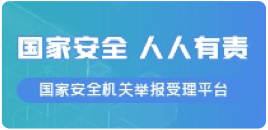

接诊后,钟强明副院长迅速组织科内会诊。在充分讨论并再次进行影像学检查后,医疗团队明确了异物的位置、大小、形态以及与周边脏器的关系,同时排除了食管穿孔及出血等并发症,确诊为“食管异物”。考虑到患儿年龄太小,情况危急,若不及时取出异物,极有可能引发食管黏膜水肿、缺血、穿孔、出血等危及生命的严重并发症,医疗团队决定立即实施异物取出术。

然而,摆在面前的困难重重。患儿食管狭小,普通内镜难以通过并抵达异物处;婴儿无法配合手术,且因无牙齿无法咬住咬口器,哭闹不停;加之年龄过小,麻醉风险极大。面对诸多挑战,阿勒泰市人民医院消化内科团队精心筹备并制定应急预案。最终,在无需麻醉的情况下,钟强明副院长凭借精湛医术,应用奥林巴斯超细胃镜,成功取出异物。整个过程仅用时几分钟,且未对患儿食管黏膜造成任何损伤,无出血、穿孔等并发症发生。

术后,婴儿生命体征平稳,食管黏膜完好,家属对医疗团队的高超医术和悉心照料感激不已。目前,患儿已无后遗症,恢复良好,很快恢复正常饮食。